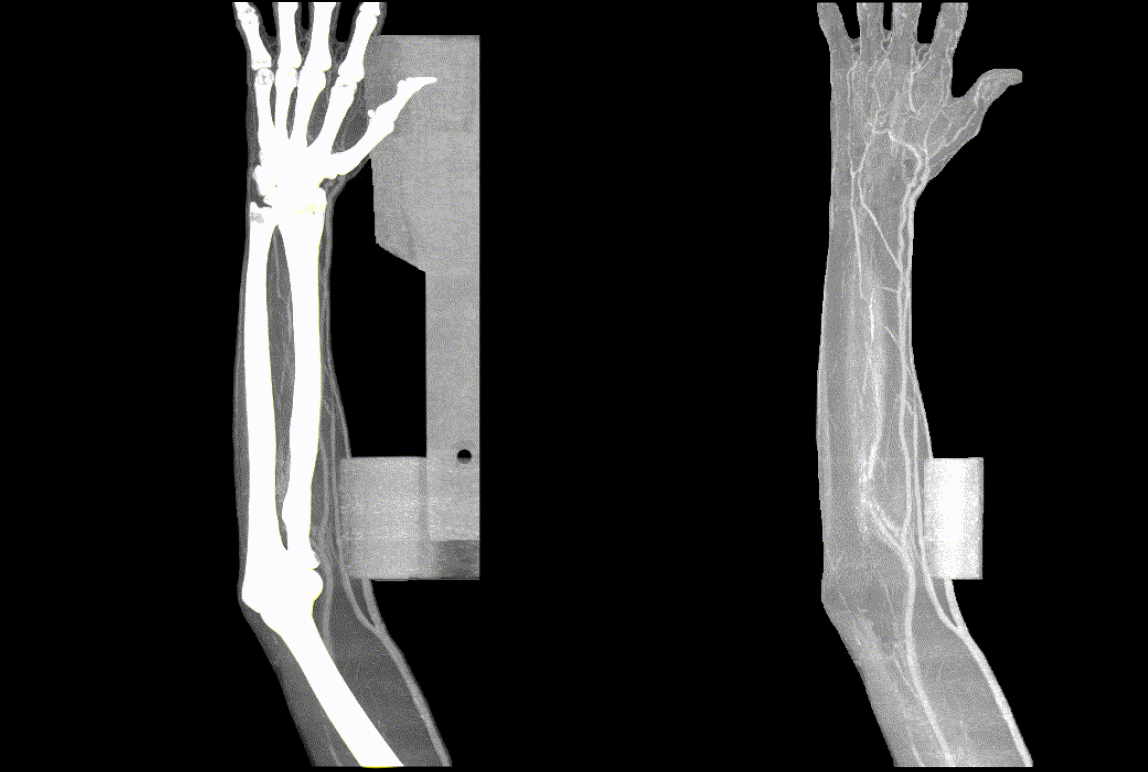

The AI model learned in this way not only shows superior performance to BAS, but also surprisingly shows that it works to some extent on images of other parts of the body other than head and neck images.

Application of ABS to upper limbs